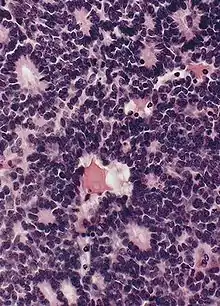

![]() | Dysgerminoma | Dysgerminoma characterized by uniform cells resembling primordial germ cells separated by fibrous septa with lymphocytes. | Category: Histopathology of ovarian dysgerminoma | Ovarian dysgerminoma |